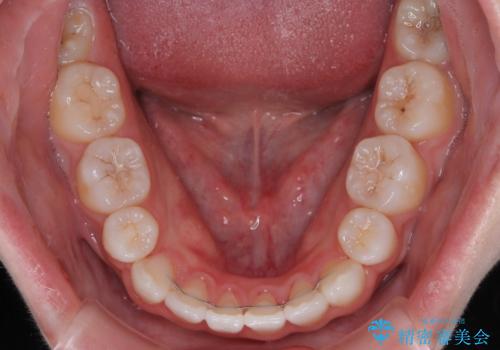

当初は舌のトレーニングをしっかりと行ってくださったおかげで、短い期間で治療を終えることができました。

- 矯正治療後の保定が不十分だと後戻り(元の位置に戻ろうとする動き)をします